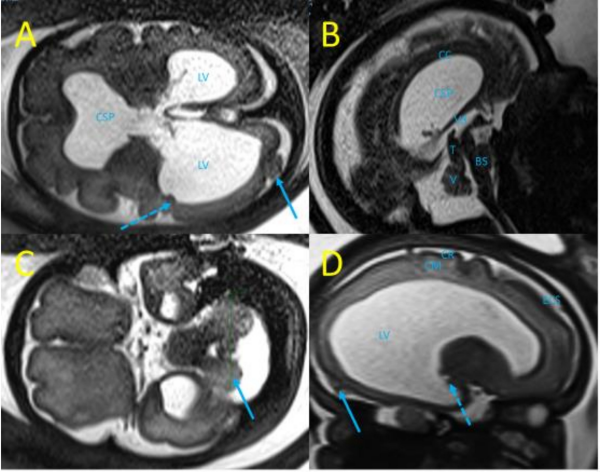

29 wg时进行的胎儿MRI证实了眼部和神经系统异常,枕骨多微脑回和室管膜下结节(图3)。经多学科讨论后怀疑先天性LCMV是这些胎儿感染症状的病因。

图3. 孕29胎儿MRI(T2加权序列)